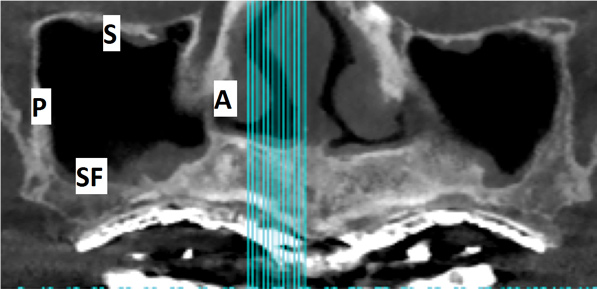

Fig 16. Maxillary sinus: panoramic view. Four of the six walls of the sinus are visible in this panoramic view: A: Anterior wall. P: Posterior wall. SF: Sinus floor. S: Superior wall.

Figure 16